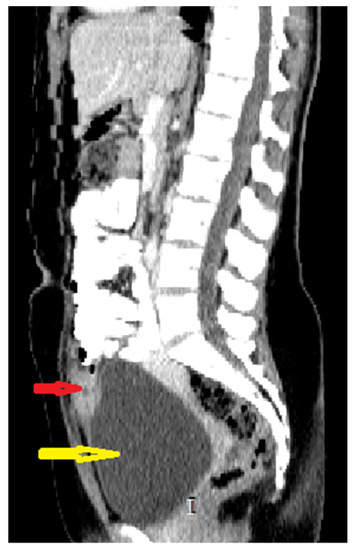

Because the radiologists requested additional investigations, an abdominal–pelvic CT scan with intravenous contrast was performed, adding an intense contrast capture in the periphery of the lesion with edema of the prevesical space (Figure 2 and Figure 3).

Figure 3. Axial CT scan of abdomen and pelvis with intravenous and oralcontrast: red arrow; supposed urachal cyst; yellow arrow: urinary bladder;green arrow: uterus; blue arrow: left ovarian cyst.